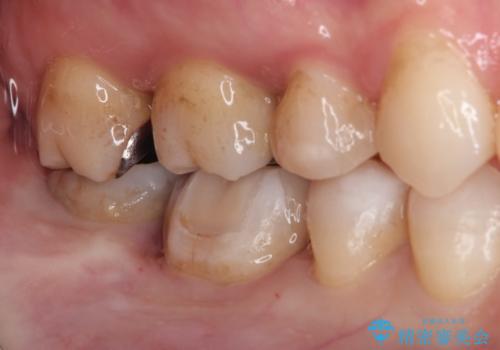

メタルフリー セラミックインレーによる治療

- 金属の詰め物を白くしたいと来院された患者様です。

セラミックインレーによって治療を行いました。

当院でのセラミックインレーはすべてe-maxと呼ばれる高強度セラミックにて製作されます。

また、製作方法もプレスと呼ばれる方法を用いることで精度を高めています。